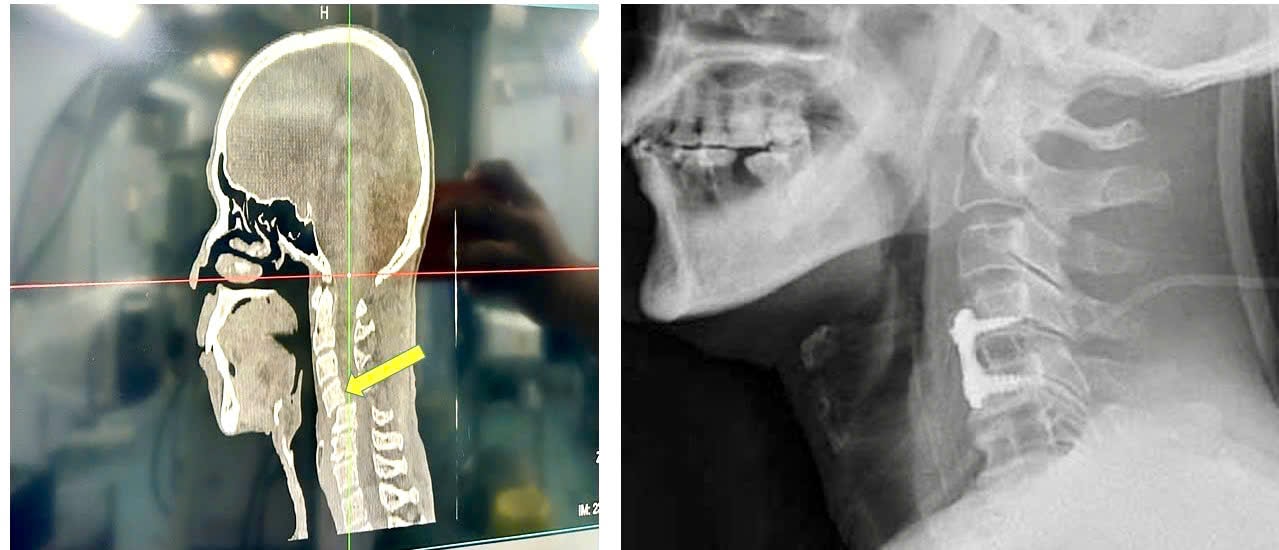

Ngay khi vào viện, bệnh nhân được nẹp cố định cột sống cổ, chụp cắt lớp vi tính và cộng hưởng từ để đánh giá tổn thương.

Kết quả cho thấy bệnh nhân bị trật đốt sống cổ C45 kèm trật cài diện khớp phía sau hai bên, dạng tổn thương nặng và hiếm gặp, chỉ chiếm khoảng 10% các ca gãy trật cột sống cổ thấp, chủ yếu ở người trên 60 tuổi.

Hình ảnh tổn thương được thể hiện rõ nét trên phần mềm trí tuệ nhân tạo AI-VinDr, giúp bác sĩ đánh giá chính xác mức độ tổn thương và lên kế hoạch phẫu thuật.

Ca mổ do BSCKII Nguyễn Tiến Dũng - Phó Giám đốc Bệnh viện trực tiếp thực hiện. Sau phẫu thuật, tổn thương đã được nắn chỉnh và cố định vững chắc, bệnh nhân không yếu liệt, không có tổn thương tủy và tiên lượng hồi phục hoàn toàn, không để lại di chứng thần kinh.